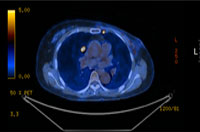

PET CT

The center utilizes advanced techniques for breast cancer diagnosis, such as fine-needle aspiration cytology, stereotactic biopsy, and Mammotome biopsy, which enhance both diagnostic accuracy and the success rate of tumor excision. Once breast cancer is confirmed, various tests are performed to determine the cancer stage. Using PET, MRI, whole-body bone scans, and chest/abdominal CT scans, the center accurately evaluates metastasis and determines the patient’s preoperative cancer stage.